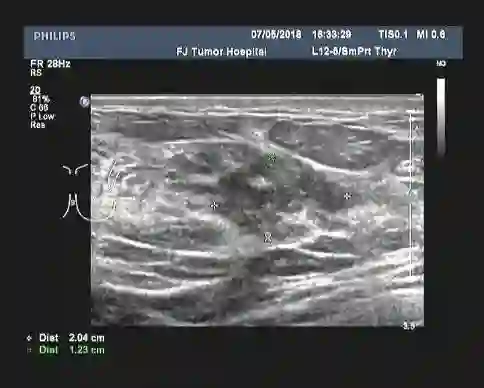

女性患者,30岁,未绝经,家族史不详(患者本人为领养)。于2018-01发现左乳肿块,当地医院乳腺MRI示:左侧乳腺外上象限可见5*7cm大小团块状影,左侧腋下可见多个肿大的淋巴结。B超提示:左乳外上象限探及一低回声区,大小约4.9cm×3.9cm,边缘不规则,可见成角、毛刺,内部回声不均;左腋上中下组探及数个低回声,大者约2.2cm×1.8cm,边界尚清,类圆形,皮髓质分界不清,皮质不规则增厚,淋巴结门消失;右乳及右腋窝未见异常。 PET-CT结果:1、考虑左乳外上象限癌累及胸大、小肌。 2、考虑左锁骨区、左胸大肌及胸小肌深面、左腋窝多发淋巴结转移。

▎疗效评估: B超(2018-04):左乳外上象限探及一低回声区,大小约4.9cm×3.9cm,边缘不规则,可见成角、毛刺,内部回声不均;左腋中下组探及数个低回声,大者约2.5cm×1.6cm,边界尚清,类圆形,皮髓质分界不清,皮质不规则增厚,淋巴结门消失;右乳及右腋窝未见异常。